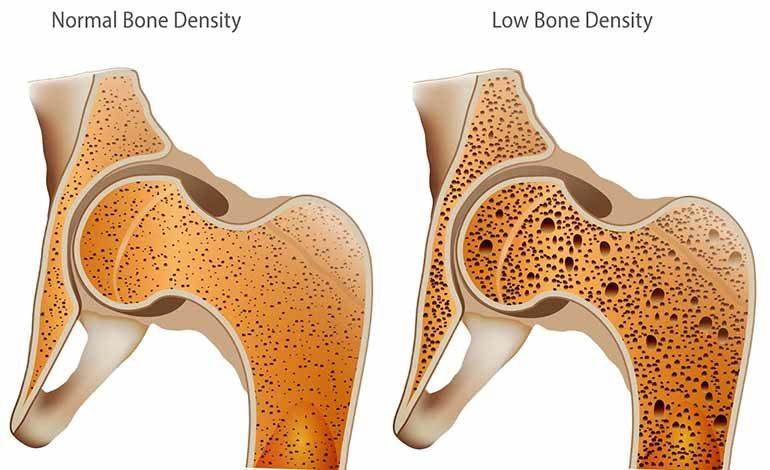

Медицинские снимки: рентген коленного сустава при остеопорозе